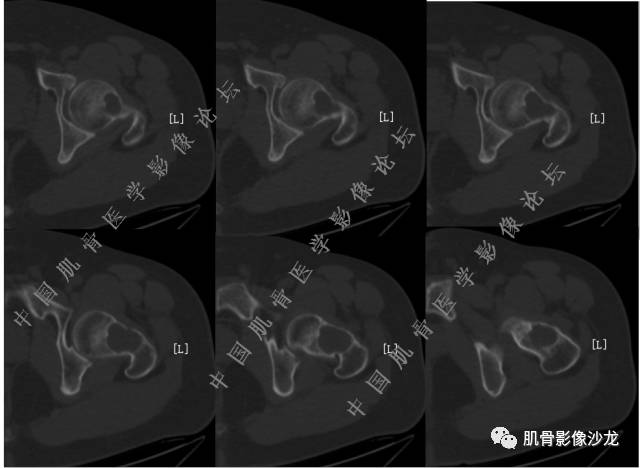

主诉:左髋疼痛1月余

现病史:患者1月余前无明显诱因出现左髋部疼痛,无明显活动受限,当地医院行X线检查,提示左股骨颈异常密度。遂来我院就诊。

既往史:曾患乙型肝炎,未正规治疗,目前无症状。

葛英霖 20:54 @肌骨沙龙义工胡俊华 你确定里面有脂肪?

葛英霖 20:5 4 常规纤维类的多一些,冠状位没有看到明显脂肪。纤维结构不良、纤维组织细胞瘤、软粘纤之类。

夏威夷的风 20:55 大方向纤维类病变

夏威夷的风 20:58 强化渐进性强化吧 边界清晰 里面也见线状低信号

飞鹰行动 21:01 良性纤维组织细胞瘤内部可以有少量脂肪

X(CT、MR)战警 21:01 泡沫细胞被吞噬后形成脂肪信号, bfh可以有脂肪条带样改变

Echo 21:04 总之这例就是各位老师说的硬化边明显,没有软组织肿块,没有侵犯,考虑良性病变,增强渐进性强化,所以考虑BFH